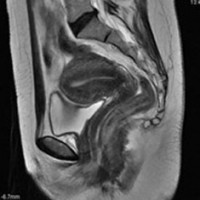

การตรวจเอ็มอาร์ไอ

เป็นการตรวจ ที่มีความชัดเจน แม่นยำมากสำหรับการตรวจ ภ